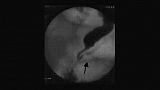

Иллюстрация №1: Cужение в терминальном отделе общего желчного протока

В нашей практике мы в основном используем УЗИ. Кроме того, при выполнении таким больным РХПГ и выявленной стриктуре терминального отдела холедоха или просто замедлении опорожнения желчных путей пациенту даются нитраты. Начало (или ускорение) их опорожнения после введения нитратов по нашему мнению с определенной степенью уверенности позволяет говорить о наличии у больного ДСО. Этот тест в определенной степени помогает дифференцировать анатомические и функциональные изменения сфинктера. В ряде случаев, казалось бы, явные стриктуры терминального отдела холедоха полностью исчезали поле применения нитратов, рубцовые сужения на введение препаратов не реагировали. На рисунках показана типичная для пациентов ДСО картина РХПГ (сужение в терминальном отделе общего желчного протока).